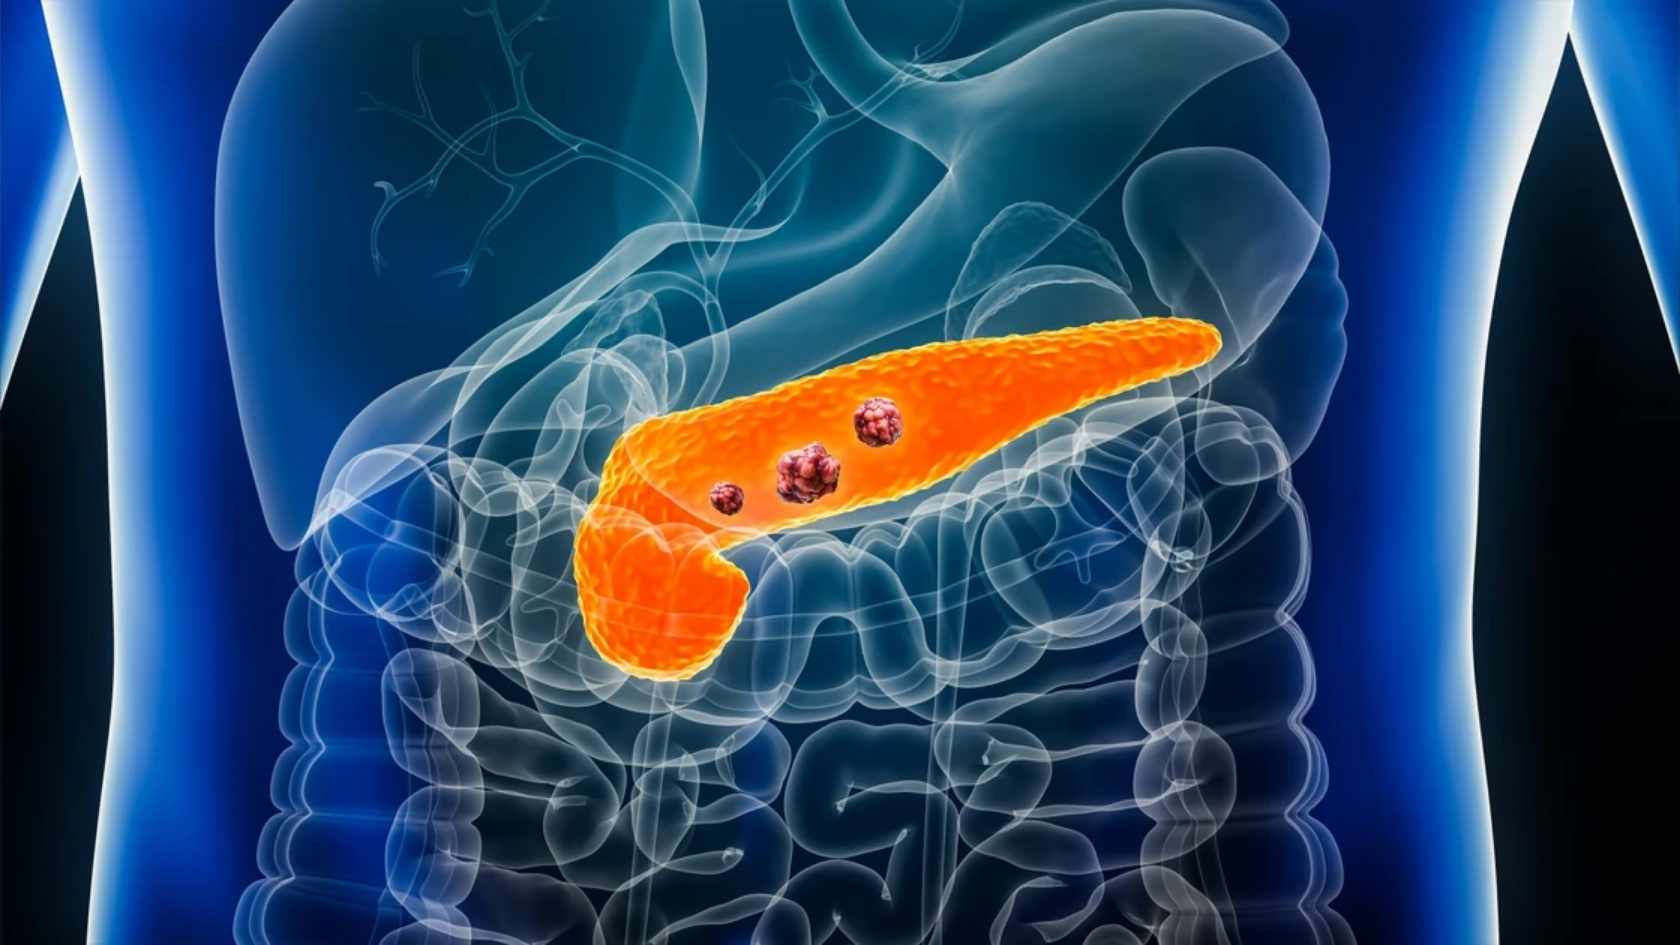

Type 2 diabetes damages your body from within. It weakens insulin response, disrupts blood sugar control, harms organs, and creates a metabolic imbalance. Standard treatment manages glucose but ignores the metabolic stress damaging your pancreas, liver, nerves, and vessels.